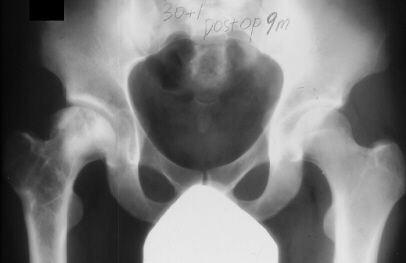

At 28 years of age, he had been having increasing pain in his right hip. He had a limp when he was tired. Positive Trendelenburg's sign was observed on the right. Internal rotation was limited to 25 degrees. All other motions were normal. X-ray showed cystic change. At the 29 years of age, he underwent bone graft of the right femoral head for degenerative cyst. At 35 years of age, only internal rotation was limited to 20 degrees. He still had pain in his hip that relates primarily to weather or to excessive walking. Only internal rotation was limited to 20 degrees. He had hip pain at the extremes of flexion and internal rotation. X-ray showed the progression of the cystic change. CT which was performed because of the question of loose bodies in the hip did not seem likely that the densities were actually in the hip joint. The antero-medial location of the cysts facing the anterior margin of the acetabulum was well depicted in CT.

28 yrs, 29 yrs, 30 yrs, 35 yrs .